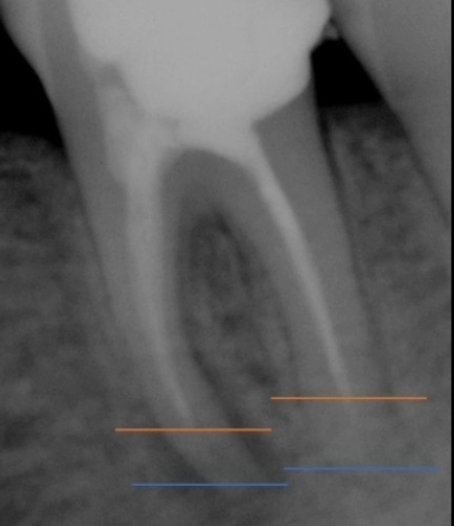

2) 뿌리 끝 염증으로 나타나는 통증

치아 신경치료 후 뿌리 끝에 염증이 생기며 통증이 나타나는 경우도 있어요. 신경치료가 잘 되었음에도 뿌리끝에 염증이 생기는 경우가 있는데요, 이는 복잡한 구조로 제거할 수 없는 근관속 염증이 뿌리끝에 모이게 되면서 잇몸이 부었다 가라앉았다를 반복하는 경우, 통증이 생기는 경우 등의 증상이 생기게 되며 치료방법으로는 치아 재식술 or 임플란트를 통해 치아의 기능을 회복하기도 해요.